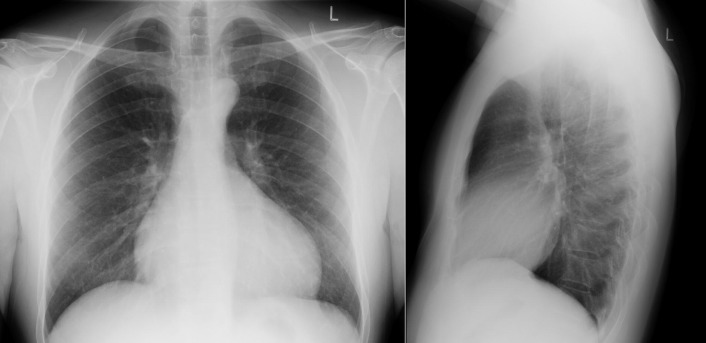

Ebstein’s anomaly. There is cardiomegaly with prominence of the right heart chambers. The appearance of the main pulmonary artery is small.

Ebstein’s anomaly. Note the marked right heart dilation, the raised apex, and the small pulmonary artery.